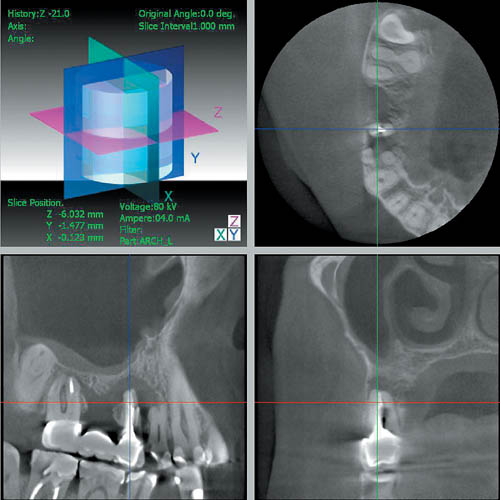

— дает возможность выявлять патологические изменения со стороны верхнечелюстных пазух, полости носа, нижнечелюстного канала (рис. 7);